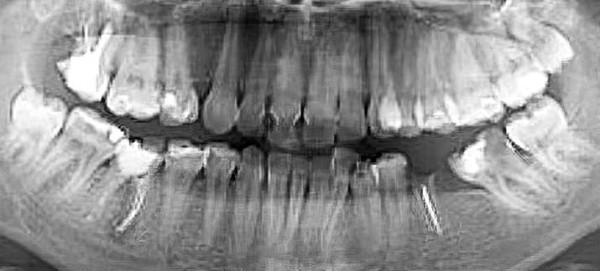

— Вот еще один пациент (см. рис. 3) с верхними «восьмерками», залегающими очень близко к верхнечелюстным пазухам, что несет большие риски при удалении. Иногда на удаление направляют пациентов с начинающими прорезываться «восьмерками», при этом показания к удалению отсутствуют, т. е. третьи моляры не препятствуют дистализации (см. рис. 4).

Рисунок 3. Ортопантомограмма 15-летнего пациента с глубоко заложенными зачатками 8-х зубов.

Рисунок 4. Ортопантомограмма пациентки 15 лет. Показаний к удалению «восьмерок» нет.